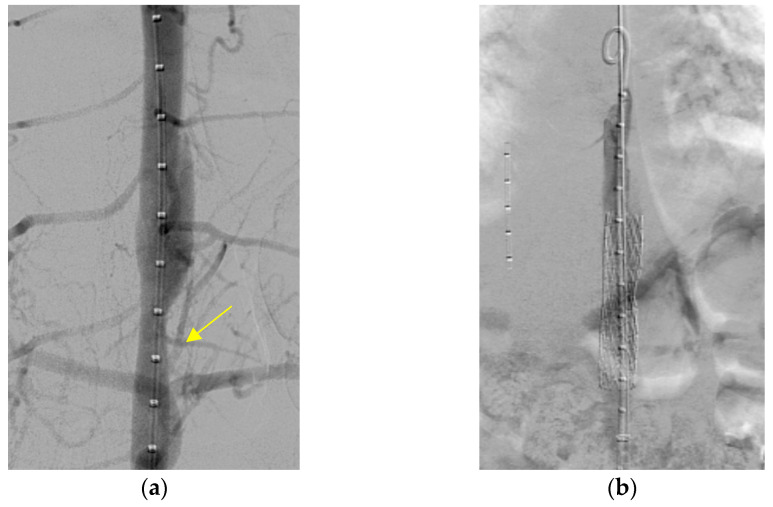

没有记录的病例导管引起的主动脉夹层的儿童患者。我们报告一个独特的情况下,儿童患者唐氏综合症谁开发了一个长期夹层主动脉瘤。患者在难以取出栓塞的动脉导管未闭装置10年后成功植入支架。唐氏综合症表现出复杂的临床情况,由于缺乏合作和不确定何时发生解剖,使得诊断具有挑战性,因为没有报告疼痛等症状。虽然在儿童中很少见,但重要的是要认识到经皮动脉导管未闭闭合后取出装置等手术是儿童主动脉夹层的潜在危险因素。

There are no recorded cases of catheter-induced aortic dissection in pediatric patients. We report a unique case of a pediatric patient with Down syndrome who developed a long-standing dissecting aortic aneurysm. The patient underwent successful stent insertion 10 years after experiencing difficulty retrieving an embolized patent ductus arteriosus device. The Down syndrome presented a complex clinical scenario, making diagnosis challenging due to a lack of cooperation and uncertainty about when the dissection occurred, as symptoms like pain were not reported. Though rare in children, it is vital to recognize procedures such as percutaneous closure of patent ductus arteriosus followed by device retrieval as potential risk factors for aortic dissections in the pediatric population.